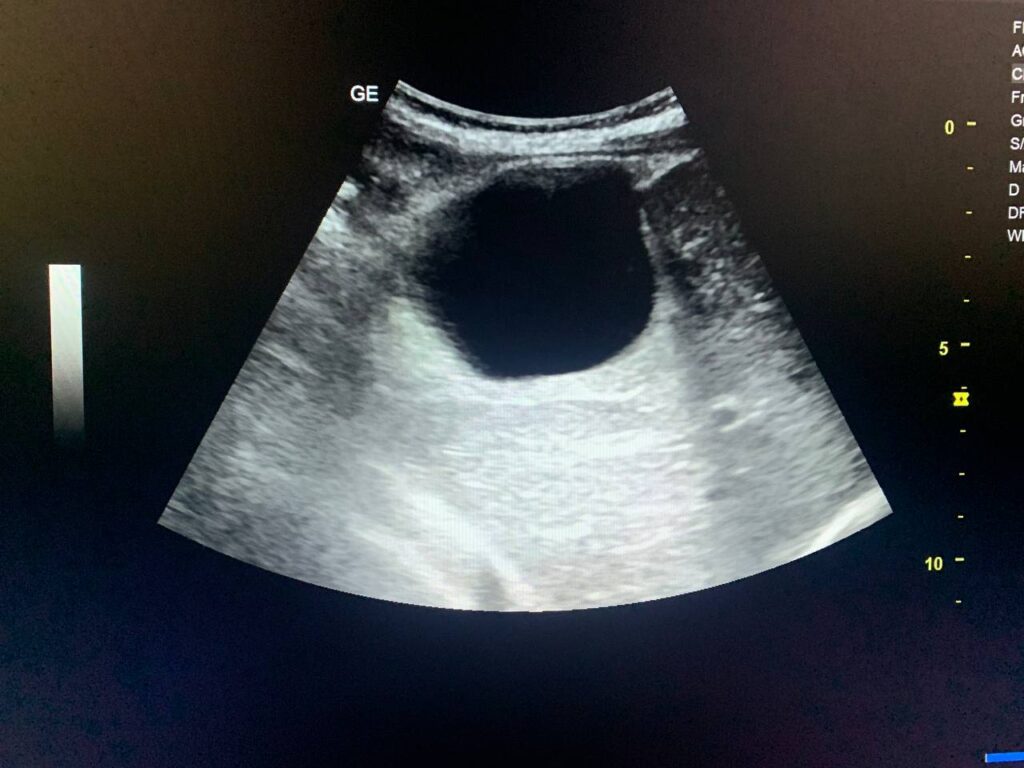

presence of circumscribed avascular cystic mass 58x47mm in the right subhepatic region ,adjacent to the right lobe segment 7 , other circumscribed avascular cystic mass 77x38mm seen in the left para cholic region , could amebic cyst ? , congenital ? others ? please for further study